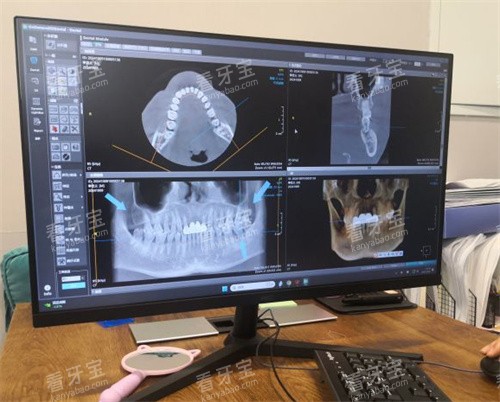

医院以高端种植牙项目为特色,有智能化技术、设备、服务和管理体系。引进了即刻种植、小创口种植、ALL - ON - 4种植、ALL - ON - 6种植等技术,其中“一日得”即刻种植技术把小创口种植、即刻负重的优势都集中起来了,能根据患者颌骨特色、骨质密度、饮食习惯等进行创新设计,不管是单颗缺牙还是全口缺牙的患者都适用。此外,还能开展全智能化种植all - on - 4,all - on - 6以及高难度穿颧穿翼种植牙技术呢。在种植牙技术领域,还采用了瑞士ITI、韩国Osstem等新型的种植系统,并结合3D智能化导板技术,实现了种植手术的精细化定位和小创口操作,既确保了种植牙的成功几率,又能减少患者的痛苦和修养时间。